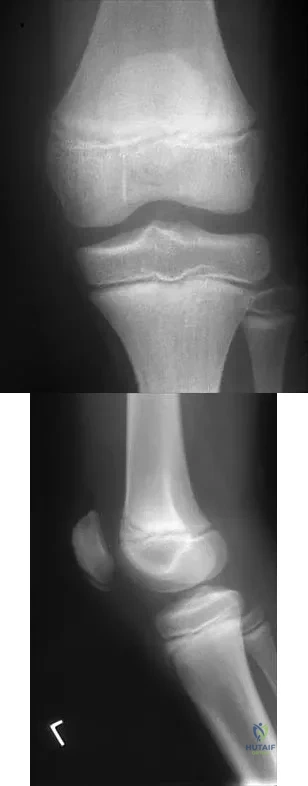

Figures 5a and 5b show the radiographs of a 45-year-old patient. What is the most likely diagnosis?

Explanation